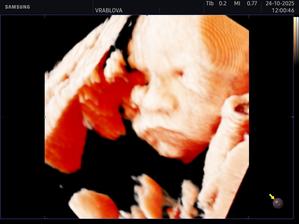

Samko 🩵🤰🏻

Môj vytúžený synček 🥹🩵 už nech ťa mám v náručí 🩵